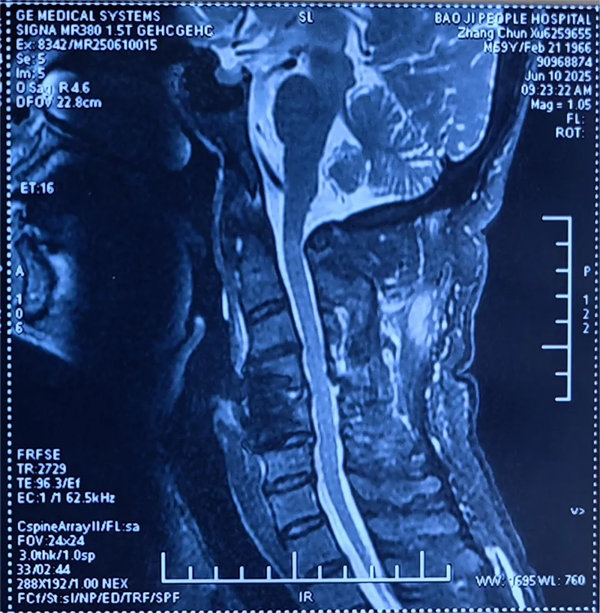

患者受傷后曾在外院接受保守治療,但肢體麻木癥狀持續(xù)存在。轉入我院時,頸椎CT及MRI顯示:頸4/5椎骨折脫位,脊髓受壓明顯,若不手術治療,可能面臨永久性神經功能障礙。我院骨四科團隊,制定了前路ACDF手術方案:通過頸前側入路,切開復位、切除椎間盤,解除脊髓壓迫,同時植入融合器、鈦板固定,重建頸椎正常序列及穩(wěn)定性。術后患者麻木感消失,復查顯示頸椎序列恢復良好,目前已康復出院。

術后